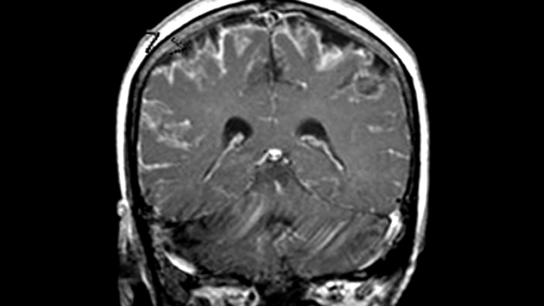

Metagenomic next-generation sequencing (NGS) of cerebrospinal fluid (CSF) obtained from patients with meningitis or encephalitis can improve diagnosis of neurologic infections.